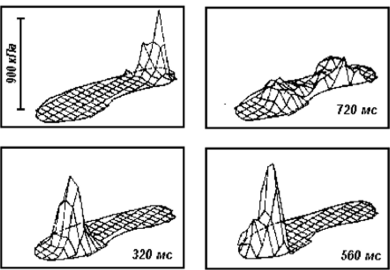

При ходьбе нагрузка на стопу меняется динамически: мы встаем на внешнюю сторону пятки, потом на внутреннюю, затем перекатываемся ближе к мизинцу, потом встаем на большой палец и затем отталкваемя пальцами, чтобы сделать следующий шаг. График распределения нагрузки схематично представлен на графике.

По время шага плантарная фасция испытывает продольное растяжение (лук пытается выпрямиться), что может привести ее к разрывам в точках крепления. В здоровой стопе разрывы не происходят благодаря динамической стабилизации стопы мышцами. НО, если у человека есть проблемы с мышцами стопы из-за плоскостопия, долгой ходьбы, многочисленных перегрузок или неврологических нарушений, то плантарная фасция может частично разорваться.

Разрывы могут случиться в разных участках плантарной фасции, поэтому боли при фасците могут быть в разных участках стопы, но чаще всего в области пятки.